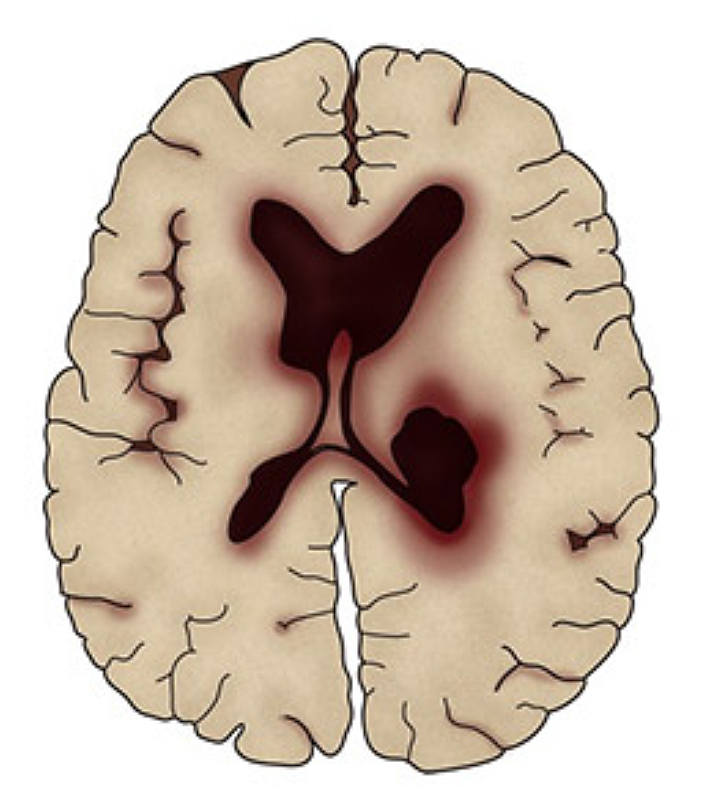

뇌에 혈액을 공급하는 혈관이 막히게 되면 뇌의 일부가 손상되는 ‘뇌경색 증상’, 뇌혈관이 터져 주변 뇌가 손상되는 ‘뇌출혈 증상’이 있습니다. 두 질병 모두 사망에 이르거나 뇌손상으로 인한 후유증이나 신체장애를 남길 수 있는 위험한 질환입니다.

한쪽 얼굴이나 사지의 감각 이상, 반신 마비, 보행장애, 구토, 의식상실, 치매 증상 등이 있습니다. 이러한 뇌졸중 전조증상을 인지했다면 곧바로 병원을 찾아 검사를 받아야 합니다. 급성 뇌경색은 골든타임 이내에 뇌혈관 중재술 등 관련 응급 치료를 받아야 마비 또는 언어 장애의 후유증을 최소화시킬 수 있다.